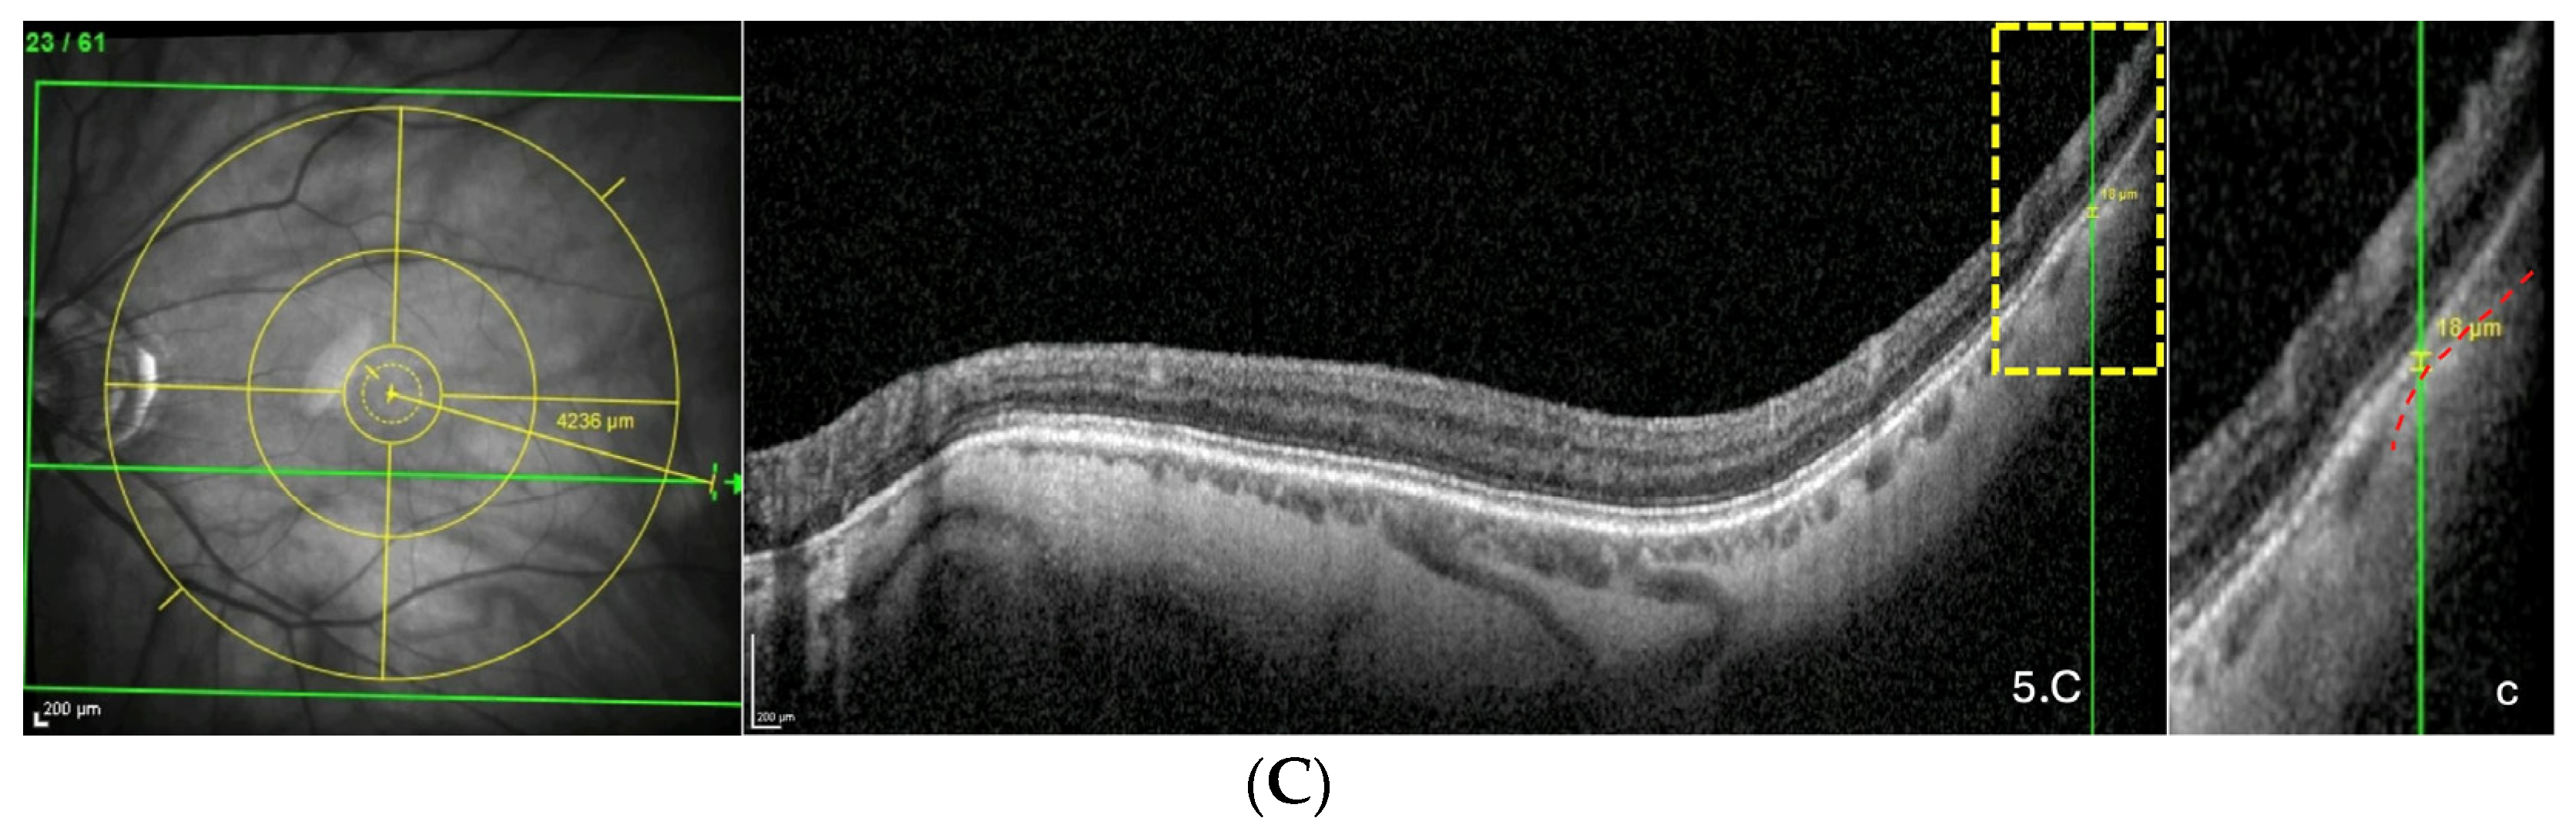

3.5. Analysis of the Distance ChT–Fovea (FT-Distance)

| Location | Sample Size (n) | Mean ± SD | Range |

|---|---|---|---|

| Overall (µm) | 78 | 3601.9 ± 93.6 | 1259–5171 |

| Superior (µm) | 23 | 3201.7 ± 163.5 | 1530–4373 |

| Along FoBMO axis (µm) | 22 | 3544.6 ± 165.5 | 1477–4587 |

| Inferior (µm) | 33 | 3918.9 ± 135.3 | 1259–5171 |